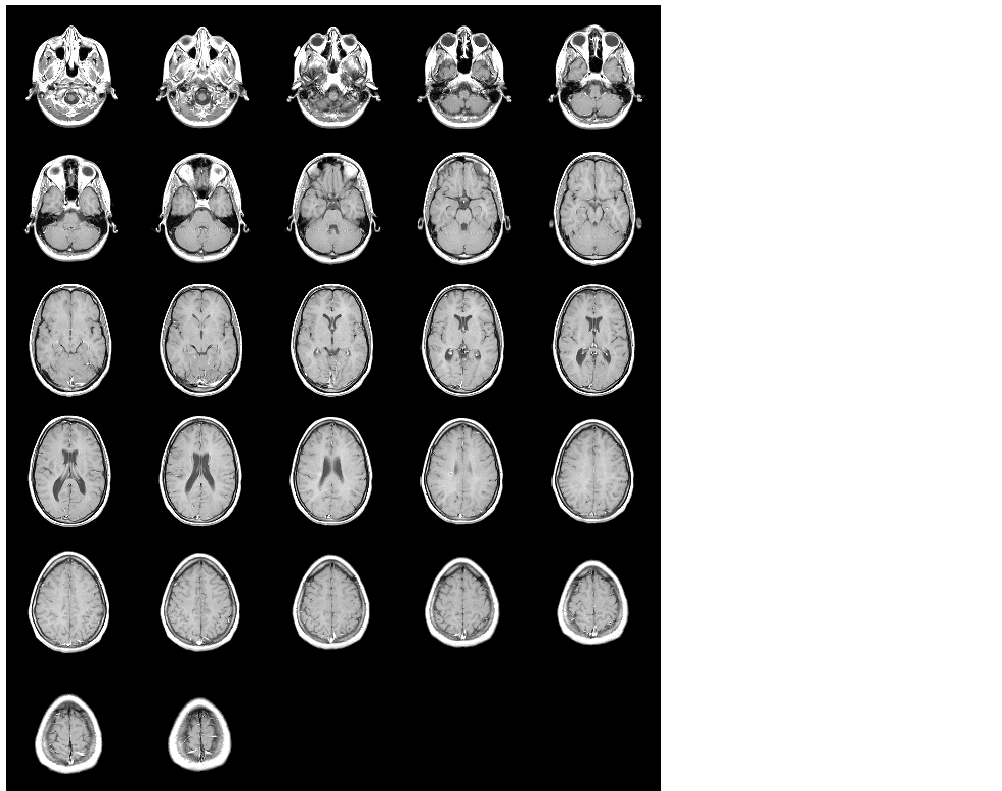

This example loads and displays all frames of a multiframe indexed image.

% Initialize an array to hold the 27 frames of mri.tif. mri = uint8(zeros(128,128,1,27)); for frame=1:27 % Read each frame into the appropriate frame in memory. [mri(:,:,:,frame),map] = imread('mri.tif',frame); end montage(mri,map);

Figure 3-3: All Frames of Multiframe Image Displayed in One Figure

Notice that montage displays images in a row-wise manner. The first frame appears in the first position of the first row, the next frame in the second position of the first row, and so on. montage

arranges the frames so that they roughly form a square.